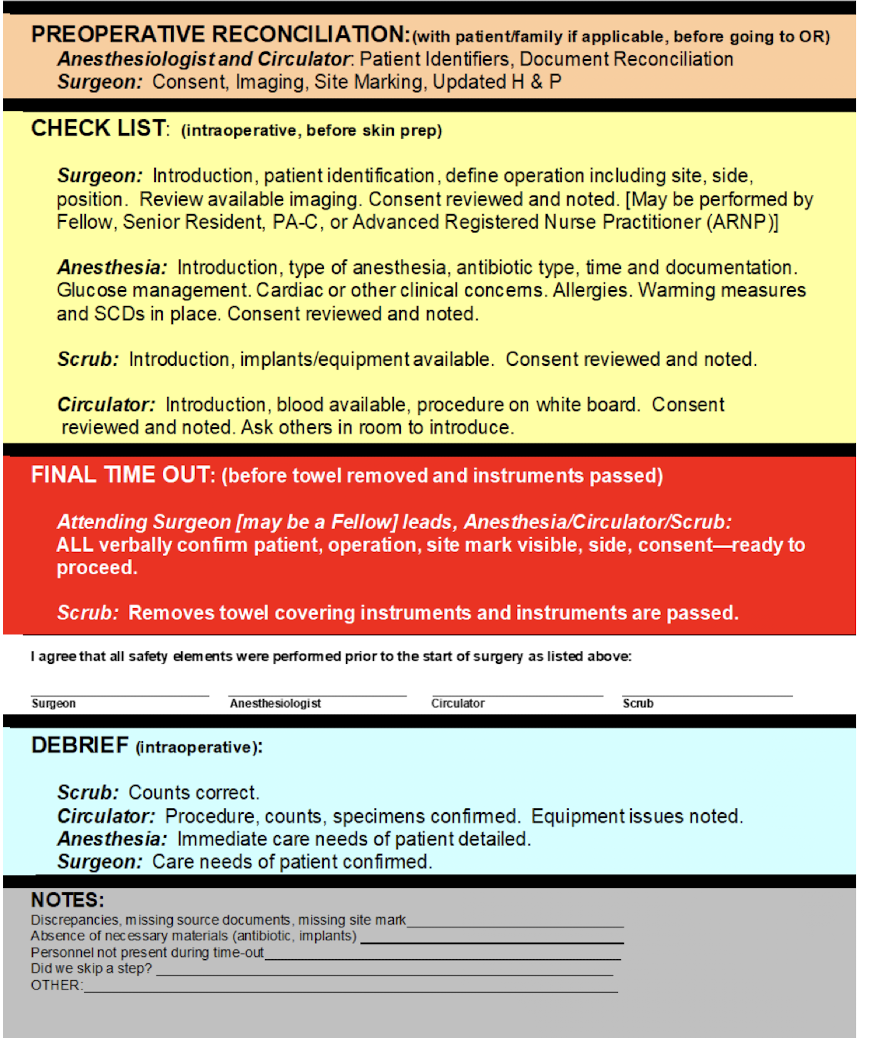

Time Out

mandatory “pause with a purpose” that reduces surgical errors

Preop Holding

• Day of surgery: update the H&P (within 30 days) + preop note

• Check for any same day/admission labs, medical updates

• Check for all consents (surgery & anesthesia)

• Pre meds & Antibiotic prophylaxis

• Discuss expectations and postop care

• Check consent, mark patient, confirm NPO status

Last opportunity to talk with patient and family